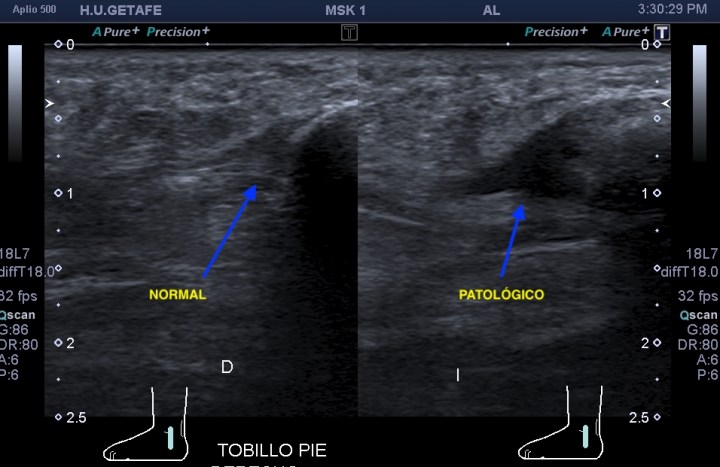

Evidentemente es una imagen patológica comparada con una normal contralateral, la anatomía de la región patológica está cambiada, el hueso está irregular, comparativamente con la zona normal. Esos cambios en el hueso se visualizan en la espina iliaca inferior, donde inserta el tendón del recto anterior, pero este tendón no solo inserta fibras ahí, sino que algunas de ellas insertan justo en la región superior del acetábulo,imagen 3, es decir, justo antes de la inserción en la espina iliaca anteroinferior, algunas se bifurcan hacia profundo, buscando el acetábulo.